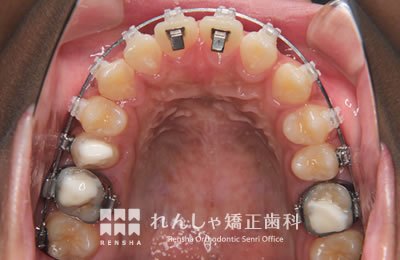

中高生

永久歯列はほぼ完成してしますが、歯列を側方だけでなく後方へも拡大し、埋まっていた右上奥歯を引っ張り出しています。

| 主訴 | 埋まったままでてこない歯がある |

|---|---|

| 診断名 | Angle Class II 小臼歯の埋伏と叢生を伴う上顎前突 |

| 初診時年齢 | 13歳5か月 |

| 装置名 | マルチブラケット装置 |

| 抜歯非抜歯 | 非抜歯 |

| 治療期間 | 2年3か月 |

| 費用の目安 | 約82万円+消費税(検査料金、都度の処置費用等も合わせた総額) |

| リスク副作用 | 歯の移動に伴う軽微な歯根吸収、歯槽骨吸収、歯肉退縮(本症例では軽度の歯根吸収を認めた)、矯正器具装着中のカリエスリスク増大(本症例ではカリエス発生無し) |